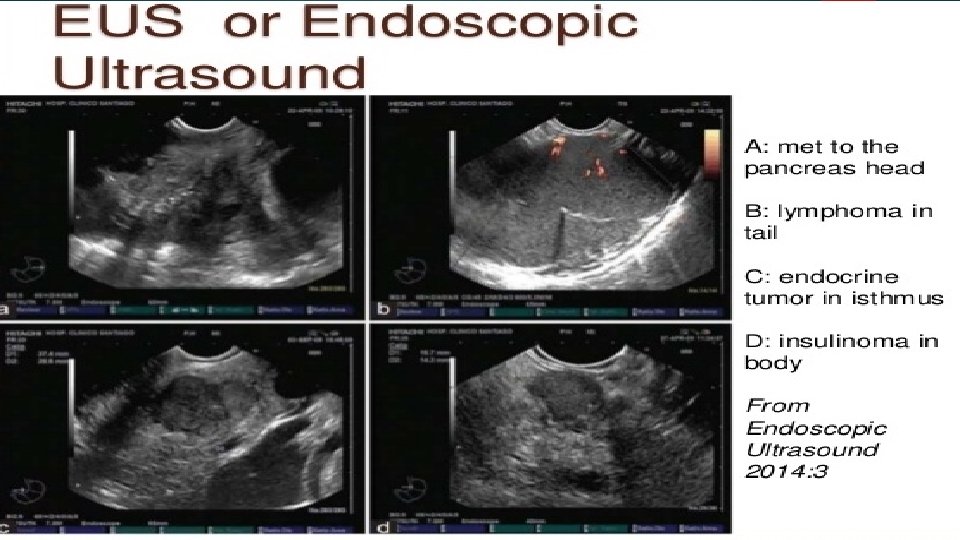

Endoscopic ultrasound technique